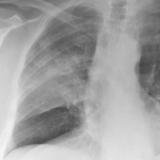

Pancoast

Album: Pancoast

Date: 03/03/2004

Size: 19 items

Views: 38262